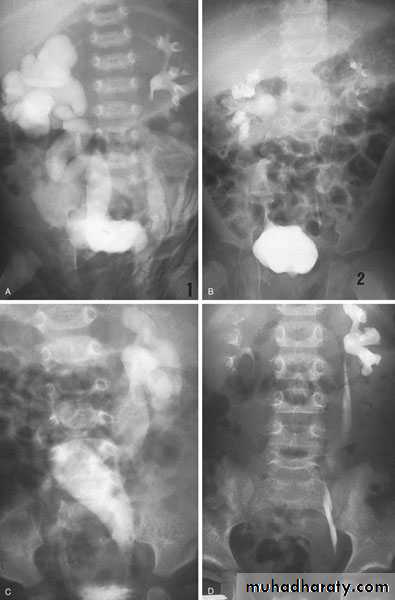

Ureteroceles

Is due to congenital atresia of the ureteric orifice which causes a cystic dilatation of the intramural portion of the ureter

Diagnosis:

IVU, cystoscopy, cystogram

The ‘adder head’ on excretory urography is typical.

Cobra (Adder) head appearance of ureterocele

Ureterocele involving single system Ureterocele involving duplicated ureter

Ureteropelvic Junction (UPJ)(PUJ) Obstruction (stenosis)